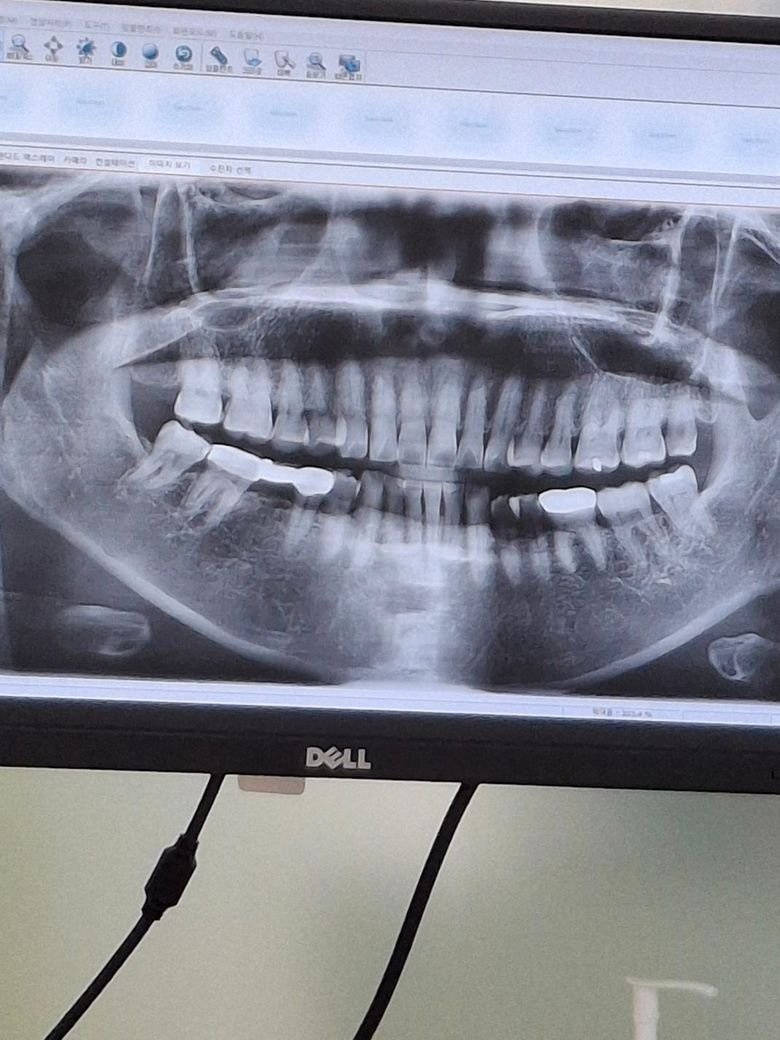

파노라마 사진을 봤을 경우에 치근단 질환이 있는 치아는 보이지 않습니다. 설측의 외골증이 있는 부분에는 잇몸이 얇게 있기 때문에 너무 딱딱한 음식을 먹거나 하면 잇몸에 상처가 생길수 있습니다.